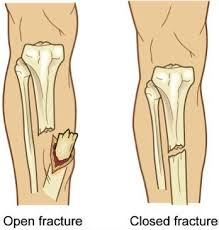

• Closed vs Open Fracture

closed - doesn't break the skin

open - break the skin + they cause more injury to local soft tissues, inc the periosteum, higher risk of infection